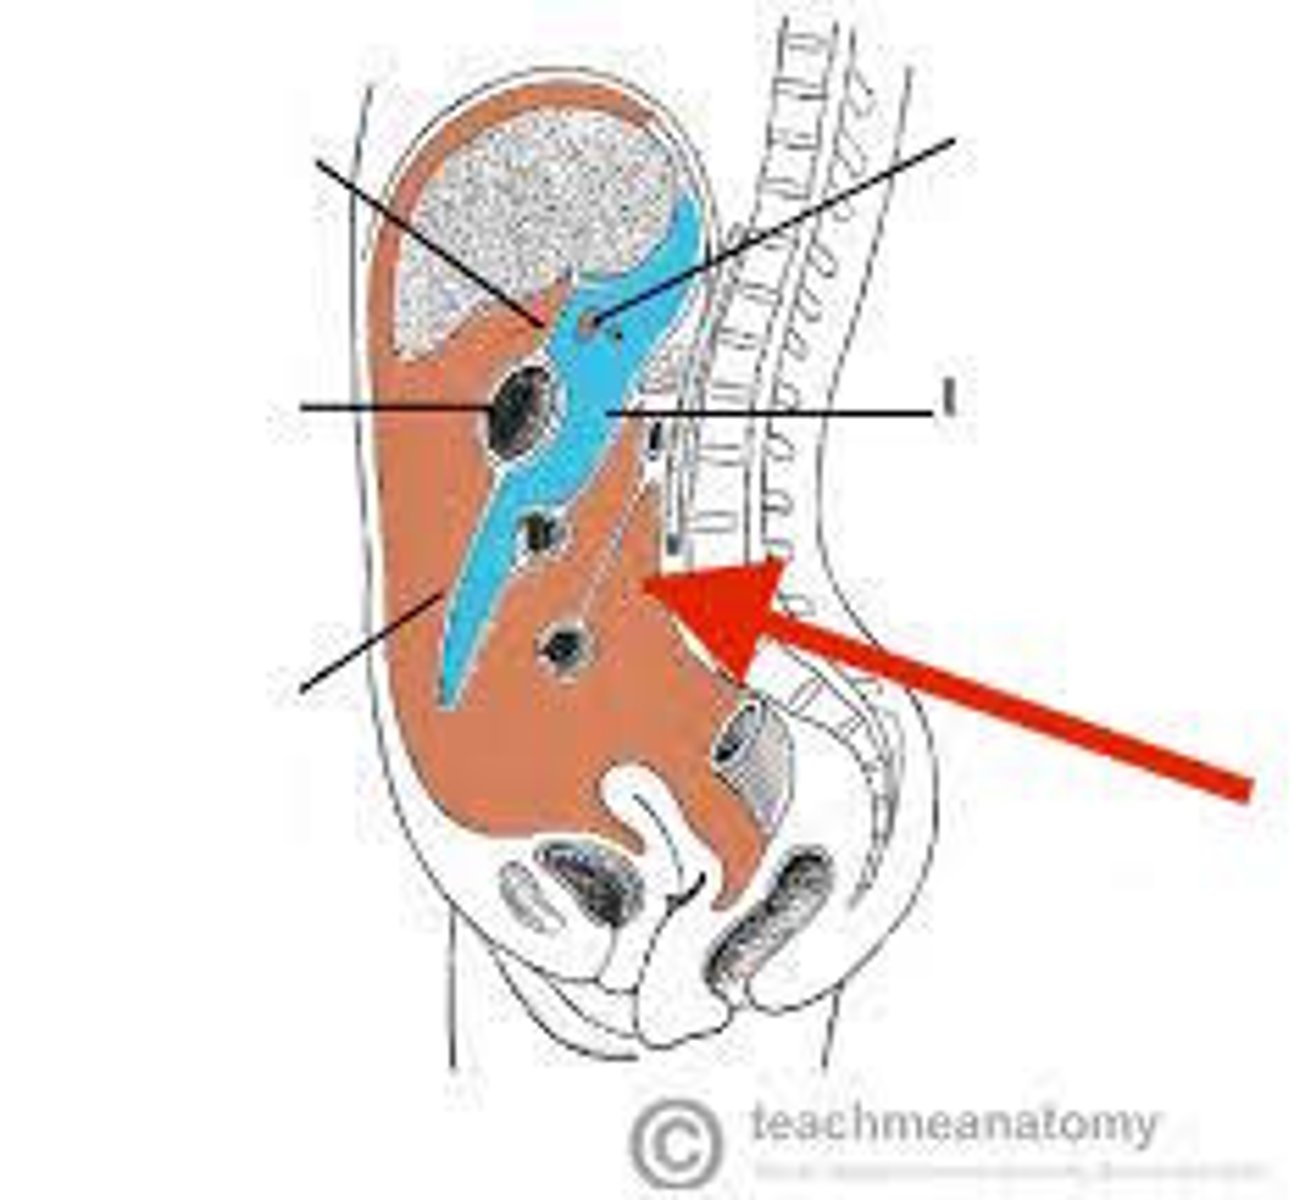

pararenal fat

perirenal fat

hilum (kidney)

left renal vein